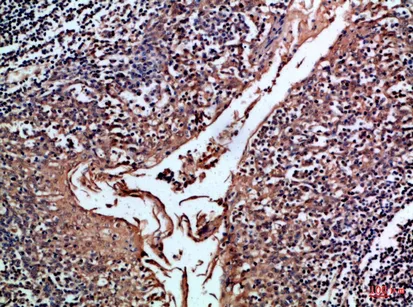

CD24 Rabbit Polyclonal Antibody($99/20μL)

Cat: APRab08302

Size1:20μL Price1:$99

Size2:50μL Price1:$118

Size3:100μL Price2:$220

Size4:200μL Price3:$380

Application:IHC-P,IF-P,IF-F,ICC/IF,ELISA

Reactivity:Human,Rat,Mouse

Conjugate:Unconjugated

Optional conjugates: Biotin, FITC (free of charge). See other 26 conjugates.

Gene Name:CD24 CD24A